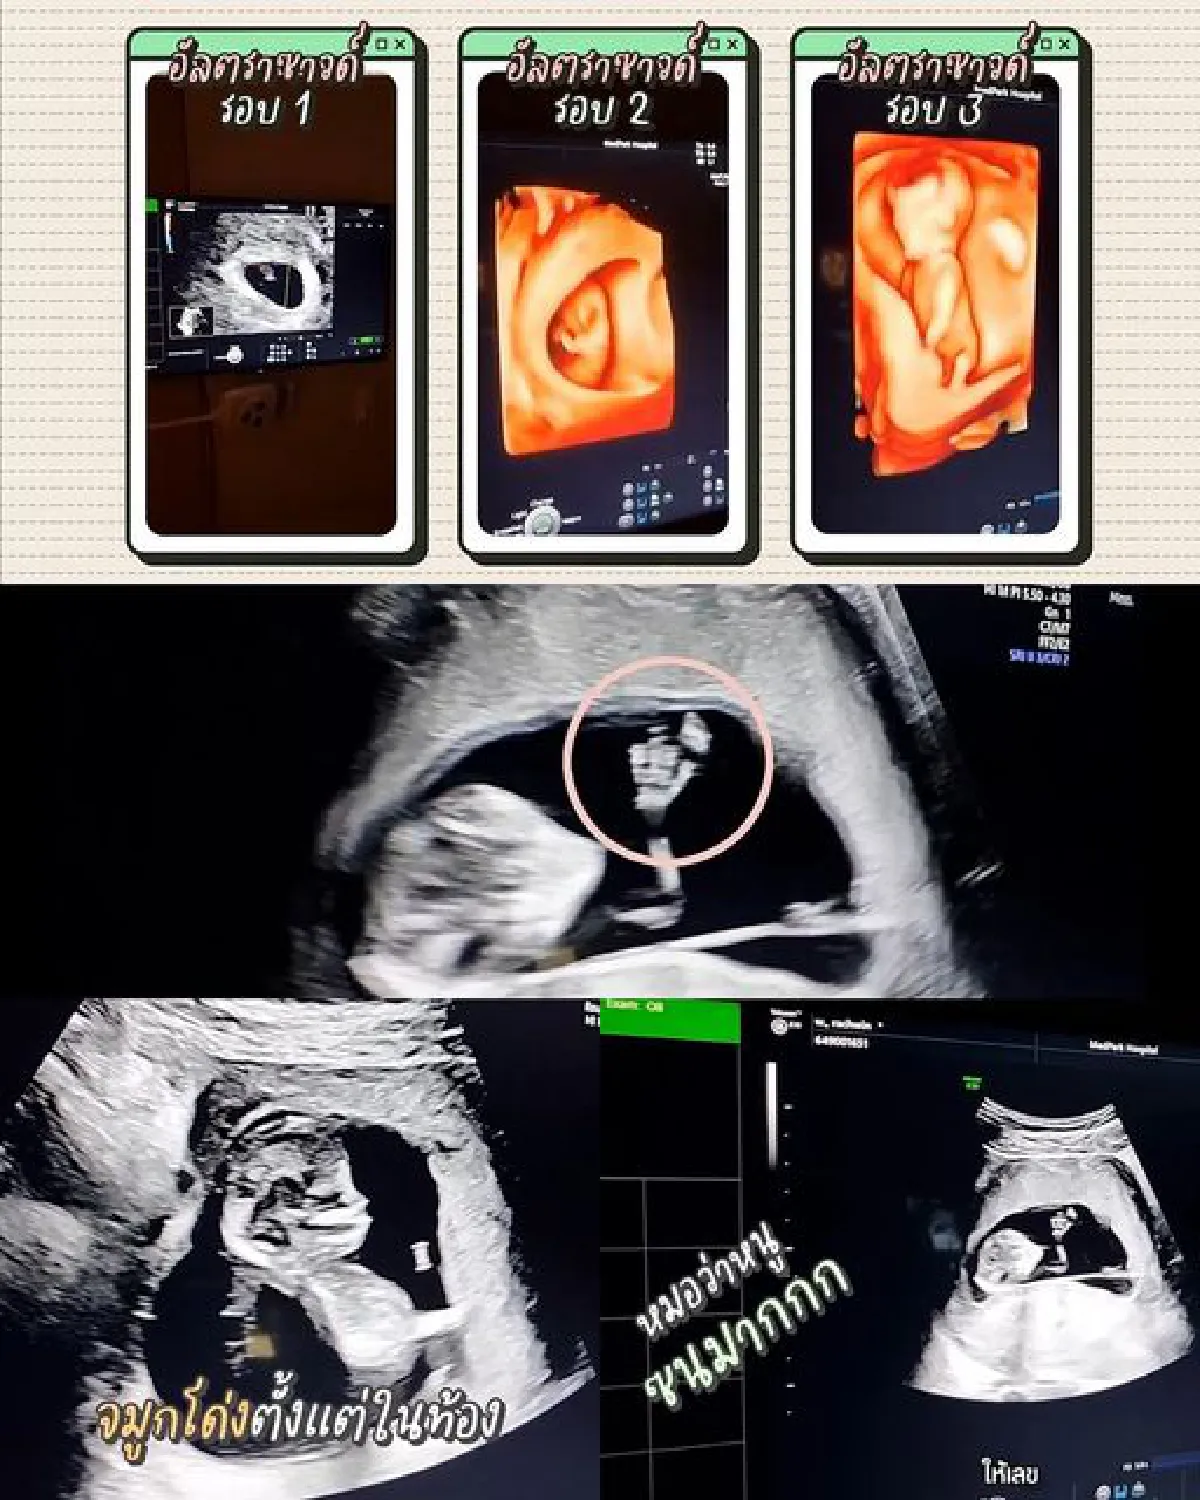

อยู่ในช่วงแฮปปี้สุดๆ สำหรับสาว “ก้อย รัชวิน” ภรรยาสุดที่รักของ “ตูน บอดี้สแลม” ที่ตอนนี้กำตั้งครรภ์ทายาทคนแรกเข้าเดือนที่ 5 แล้ว ท้องก็เริ่มขยายใหญ่จนเห็นได้ชัดเจน งานนี้หลายๆ คนต่างพากันคาดเดาไปว่าทายาทคนแรกของทั้งคู่นั้นจะเป็นชายหรือหญิง